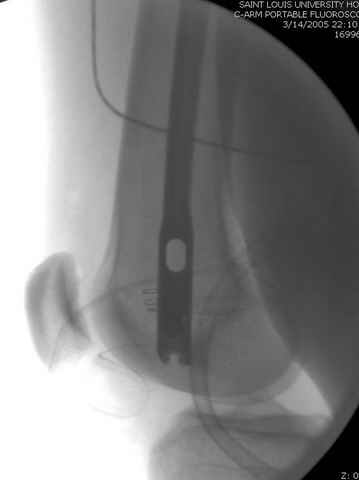

По поводу открытого перелома больной ургентно взят на ретроградное интрамедулярное штифтование, после рутинного дебрайдмента и фасциотомии на бедре и на голени.

перелом бедра

интраоперационные

снимок монитора